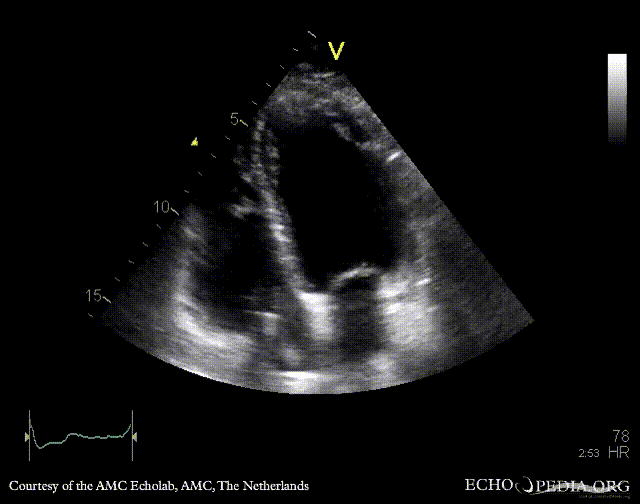

Endocarditis of pacemaker lead

PSAX: mobile structure on pacemaker lead A4CH: mobile structure on pacemaker lead